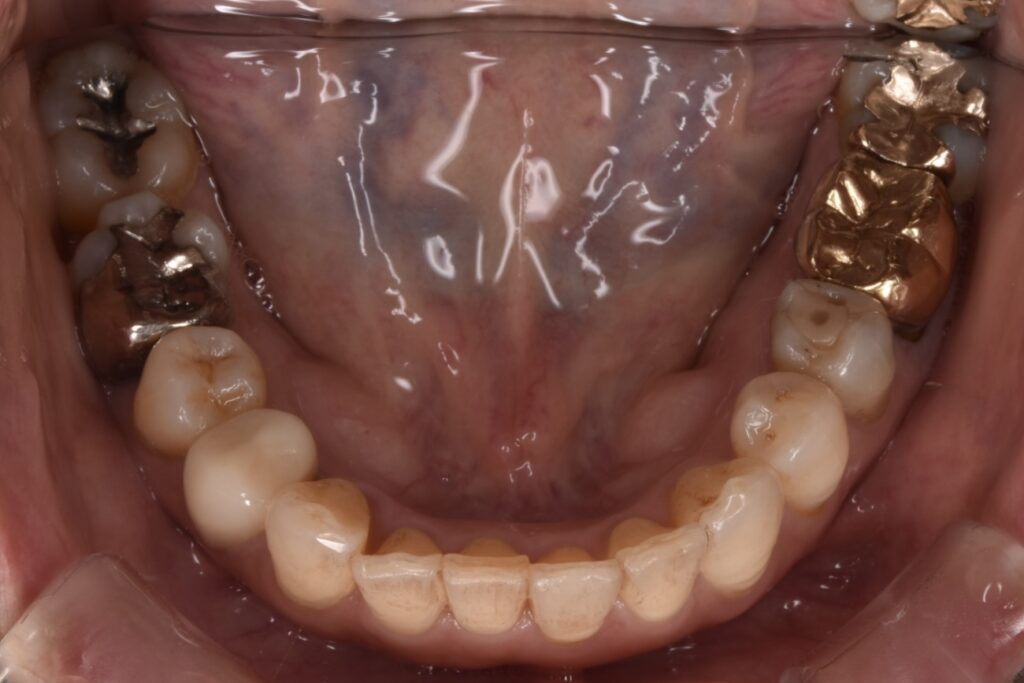

矯正前

前歯を中心に叢生(ガタガタ歯並び)がみられます。

矯正前の横顔や正面、咬合面の写真です。